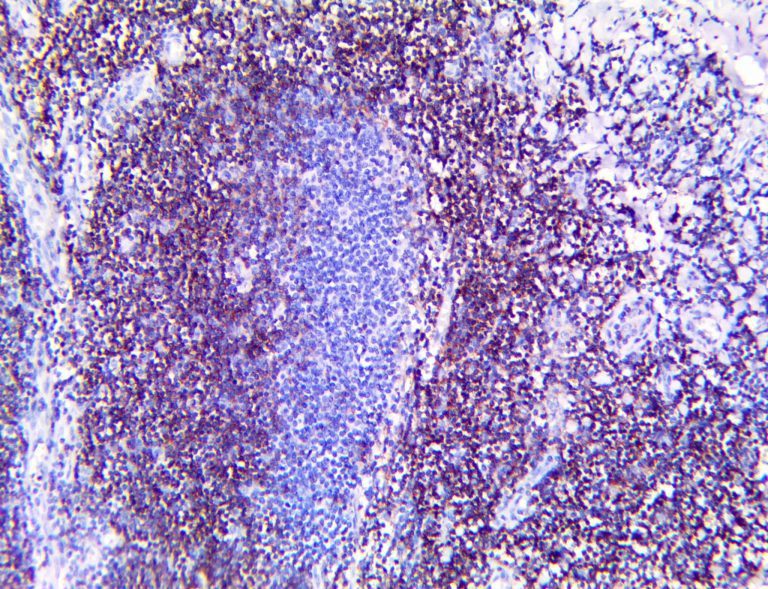

The first cytokines released are interleukin 1β (IL-1β) and tumor necrosis factor-α (TNF-α), which attract a variety of circulating white blood cells (WBCs) to the infection site, including neutrophils, monocytes, macrophages, and natural killer (NK) cells. This response, along with the antipathogenic chemicals released by these cells (i.e., complement), comprise the innate immune response. These cells directly attack the invading pathogen and also release additional cytokines, chief among them interleukin-1 and 6 (IL-6). IL-6 is essential for invoking the adaptive immune response, which calls T-cells, B-cells, and T helper (Th) cells to the infection site. IL-6 also stimulates further recruitment, proliferation and activation of macrophages.

It is the ICU physician who is most likely to witness one of the deadliest manifestations of the abnormal immunological response, the cytokine storm syndrome (CSS). This response is also referred to by some as the cytokine release syndrome (CRS). CSS is characterized by continuous activation and expansion of macrophage and lymphocyte populations, which secrete large amounts of cytokines, causing the cytokine storm. This massive cytokine release is akin to hemophagocytic lymphohistiocytosis (HLH) disease, a syndrome characterized by initial unchecked and persistent activation of cytotoxic T lymphocytes and NK cells.